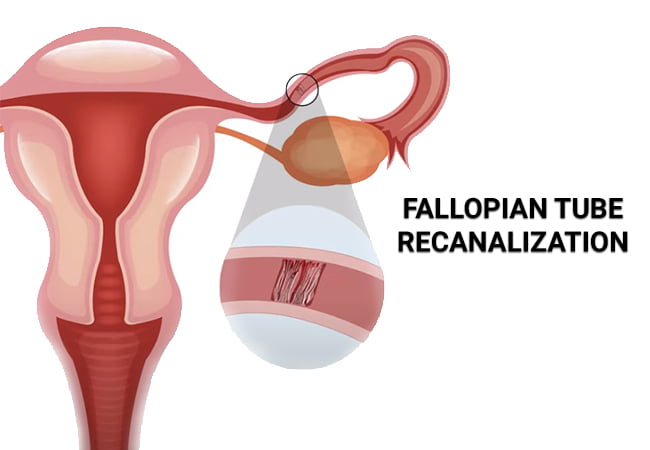

Fallopian Tube Recanalization